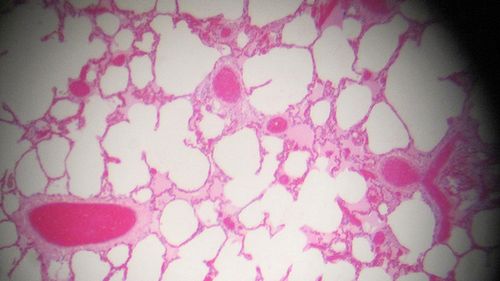

Oddajesz kilka (tu uwaga!) MIKROlitrów krwi (a nie MILIlitrów), czekasz kilka minut i już wiesz, czy masz poważne kłopoty ze zdrowiem. Test do wykrywania markerów nowotworowych opracowany przez naukowców z Brigham Young University działa naprawdę szybko. A ma być jeszcze szybszy.

Twórcy urządzenia do szybkiego wykrywania raka pracują nad przyspieszeniem jego działania, by skrócić czas oczekiwania na wynik z uzyskiwanych obecnie ok. 30- 40 minut do zaledwie 10. Nowy test wygląda zwyczajnie: ot, przezroczysta płytka.

Do wykrywania markerów nowotworowych wykorzystuje się tu tylko jedno przeciwciało (a nie kilka – jak ma to miejsce w innych testach) i prąd elektryczny, przepuszczany przez urządzenie. Po szybkości ruchu białek znajdujących się w badanej próbce szacuje się wyniki.

Amerykański wynalazek działa podobno lepiej niż popularny system ELISA – jeden z najpopularniejszych testów używanych w diagnostyce medycznej i w badaniach naukowych. Nowy, przenośny test umożliwia wykrywanie wielu markerów.